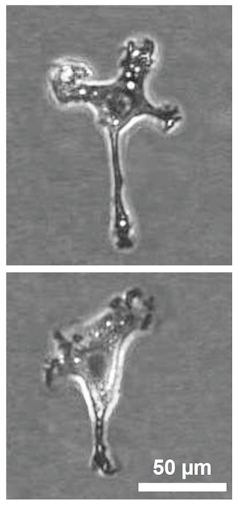

Macrófago atacando bacterias patógenas. Corona Borealis Studio/Shutterstock

Las múltiples funciones de los macrófagos abarcan tanto aspectos inmunológicos como no inmunológicos. En primer lugar, son expertos en fagocitosis, el proceso mediante el cual engullen y destruyen partículas extrañas, células muertas y restos celulares. Esta capacidad los convierte en una primera línea de defensa contra infecciones bacterianas, virales y fúngicas.